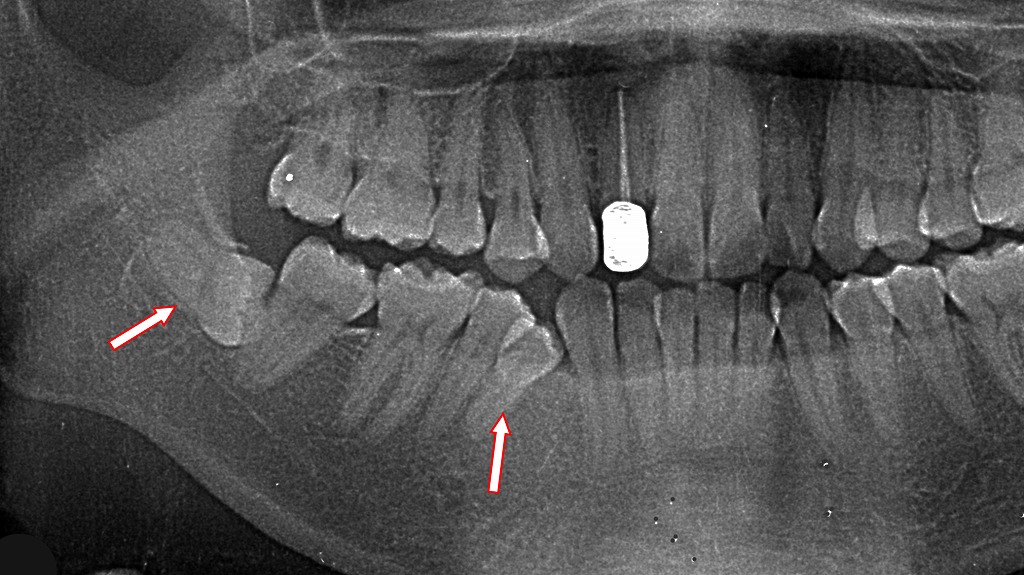

- 1.4. 臼歯部の叢生のパノラマX線写真

- 1.4.1. 🦷 全体の診断所見

- 1.4.1.1. 右下第4小臼歯(右下4番)

- 1.4.1.2. 右下第5・6・7歯(小臼歯〜大臼歯)

- 1.4.1.3. 右下智歯(親知らず・8番)※左の矢印

- 1.4.2. 🔍 問題の因果関係まとめ

- 1.4.3. 🩺 治療上の考慮点